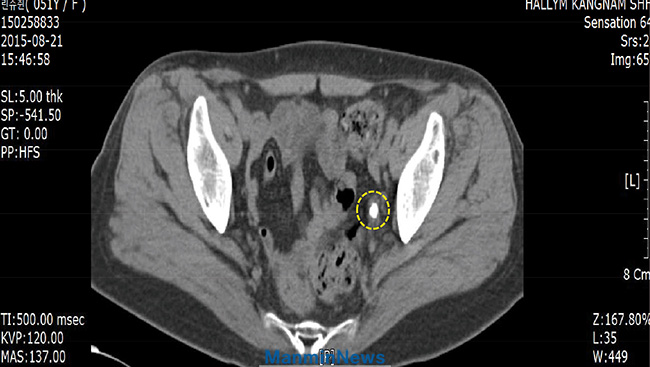

Before the prayer_ The urinary stone, 1.3cm in size in left ureter

After the prayer_ The stone is not seen